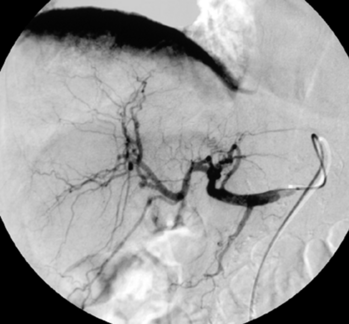

Digitale Subtraktionsangiografie: Superselektive Sondierung und Darstellung der mutliplen Blutungsherde. Die Leberarterien werden durch die zystischen Metastasen ausgespannt.

Digitale Subtraktionsangiografie: Nach Spiralembolisation mehrerer Subsegmentäste der A. hepatica stehen die zahlreichen Blutungen.